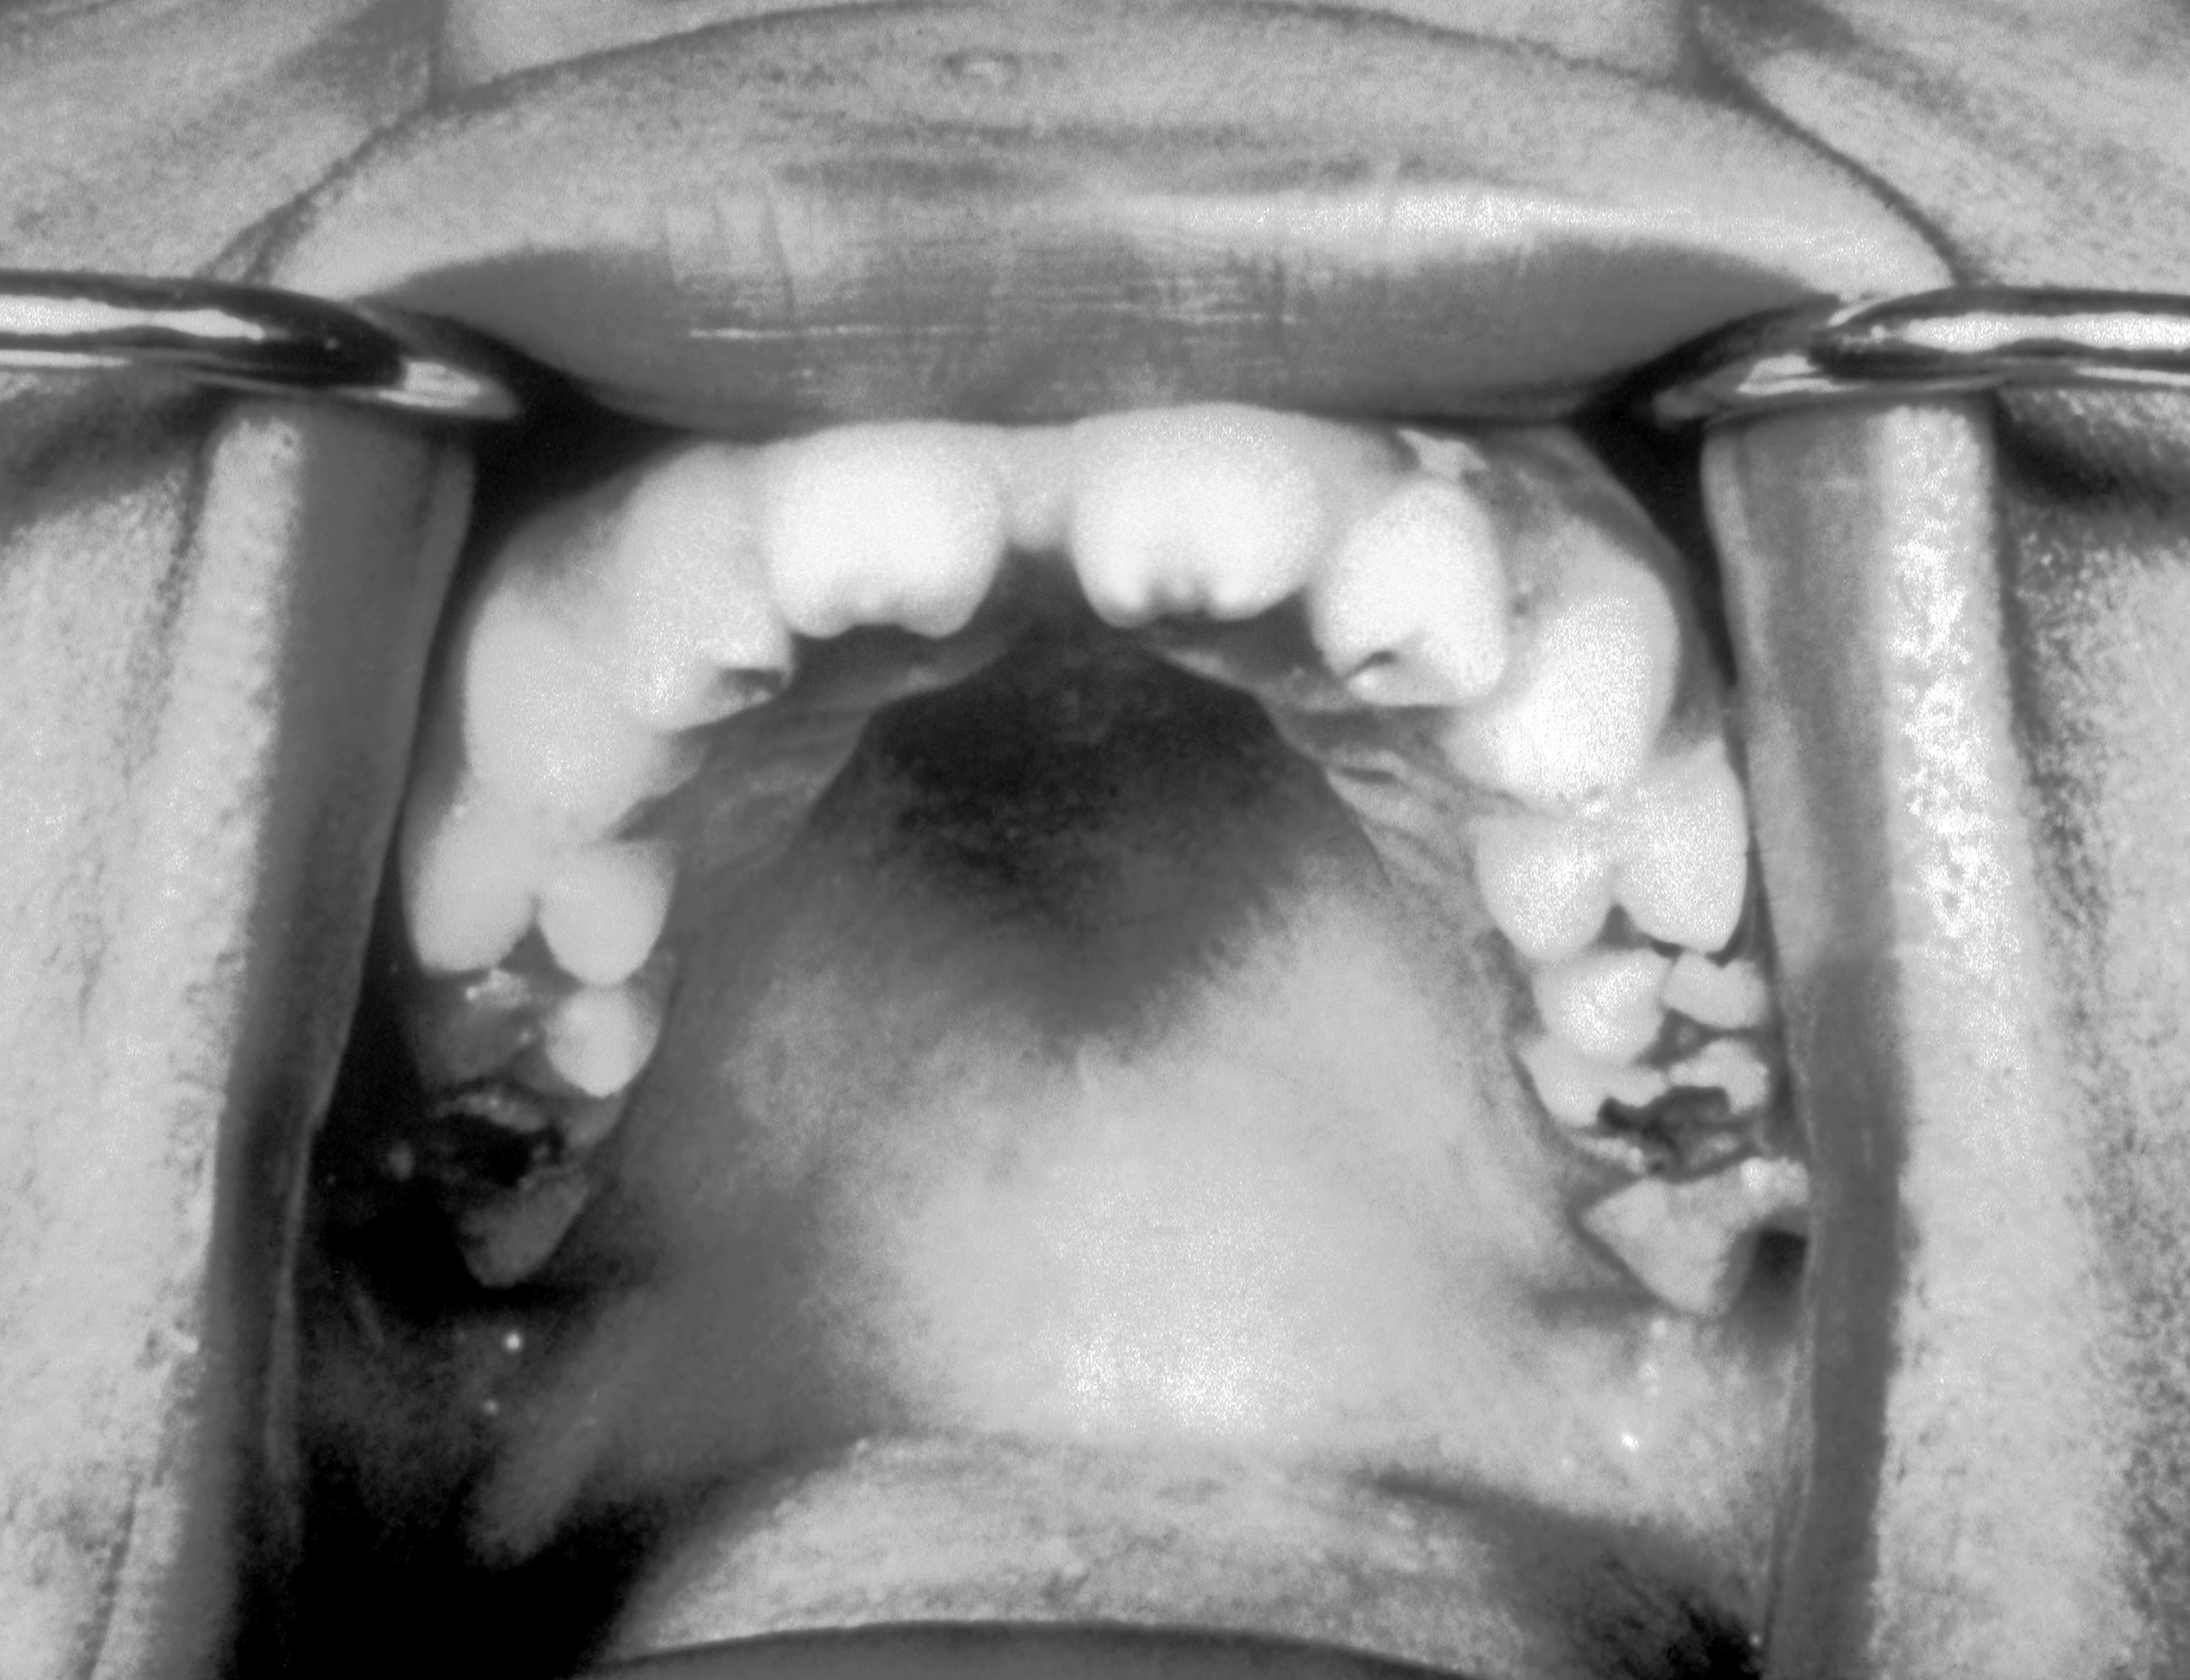

Hutchinson’s Triad is a clinical syndrome consisting of three characteristic symptoms: specific dental anomalies, interstitial keratitis, and damage to the auditory nerve. This triad occurs as a result of congenital syphilis, which is transmitted from mother to unborn child during pregnancy. The disease causes severe damage already in the uterus. The dental anomalies arise from a disturbance in tooth development during the calcification of the incisors, leading to a characteristic deformity. These teeth are smaller, flatter, and often have a central notch.

The deformation of the teeth due to syphilitic damage begins in the uterus when the infection impairs tooth formation. The bacterium Treponema pallidum causes these malformations during pregnancy, which manifest later in the child’s life. The affected teeth, particularly the incisors, remain smaller, with their edges flat and notched.

In the skulls I’ve examined from archaeological digs in England, these dental deformities are not rare. What’s particularly impressive is how these deformities can provide insights into the health and life of individuals. A single tooth can give us clues whether a person suffered from severe health issues in childhood that persisted into adulthood. These problems were not limited to the appearance of the teeth, but often indicated underlying medical complications affecting the entire organism.

A particular aspect of my work is the ability to link such dental anomalies with other pathological findings. Skulls showing syphilitic dental deformities often also exhibit other signs of the disease, like bone damage or systemic inflammations, which are typical for advanced syphilis. This combination of findings allows for a detailed reconstruction of an individual’s disease history. What’s interesting is not just the dental deformity itself, but also how the disease affected the whole body.